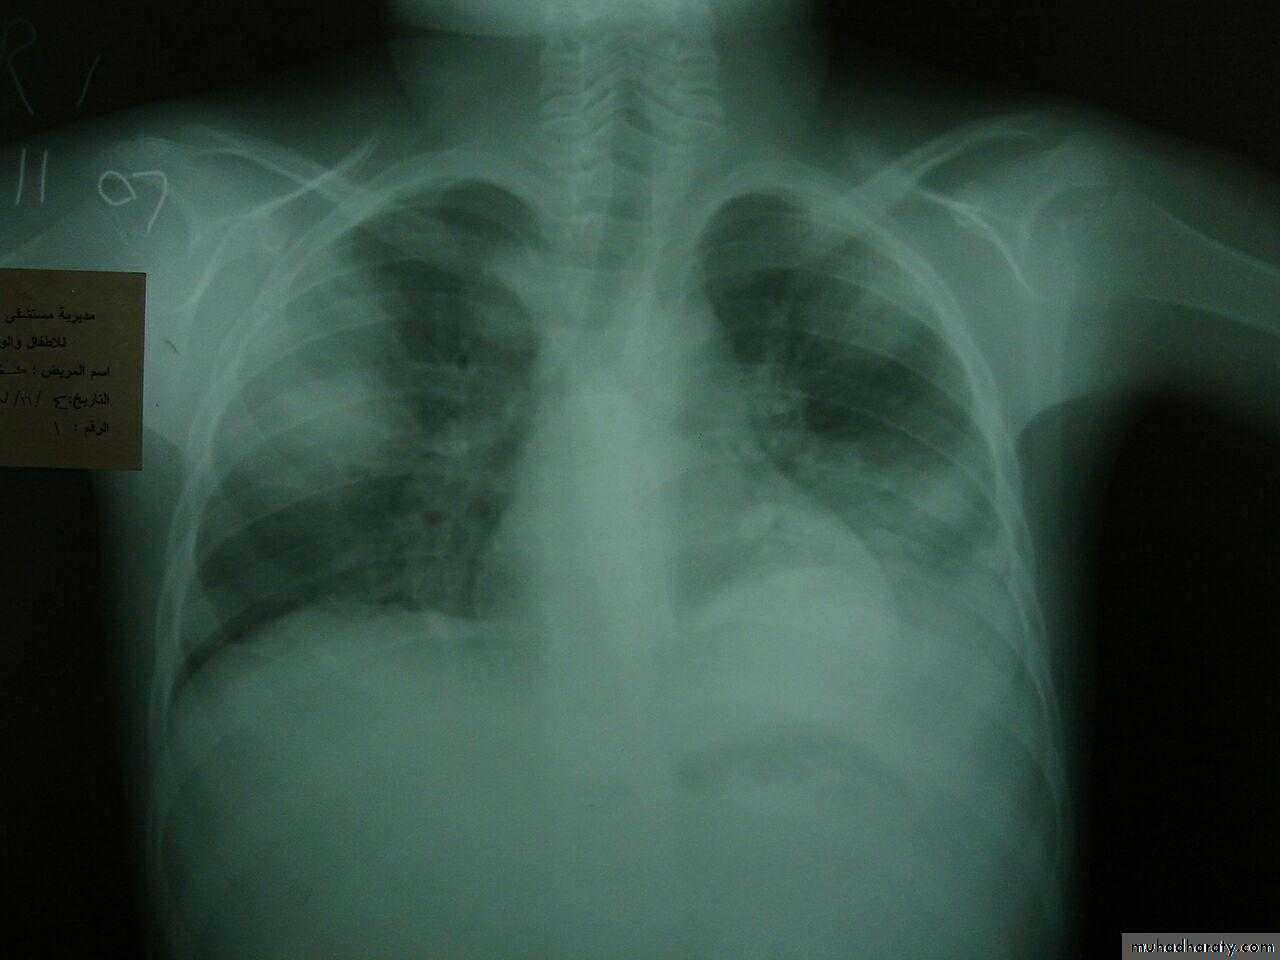

Cardiomegaly

Oligemic lung (devoid vascularty of lung )

Elevation of heart apexRt. Sided aortic notch

BOOT SHAPE HEART ( TOF )